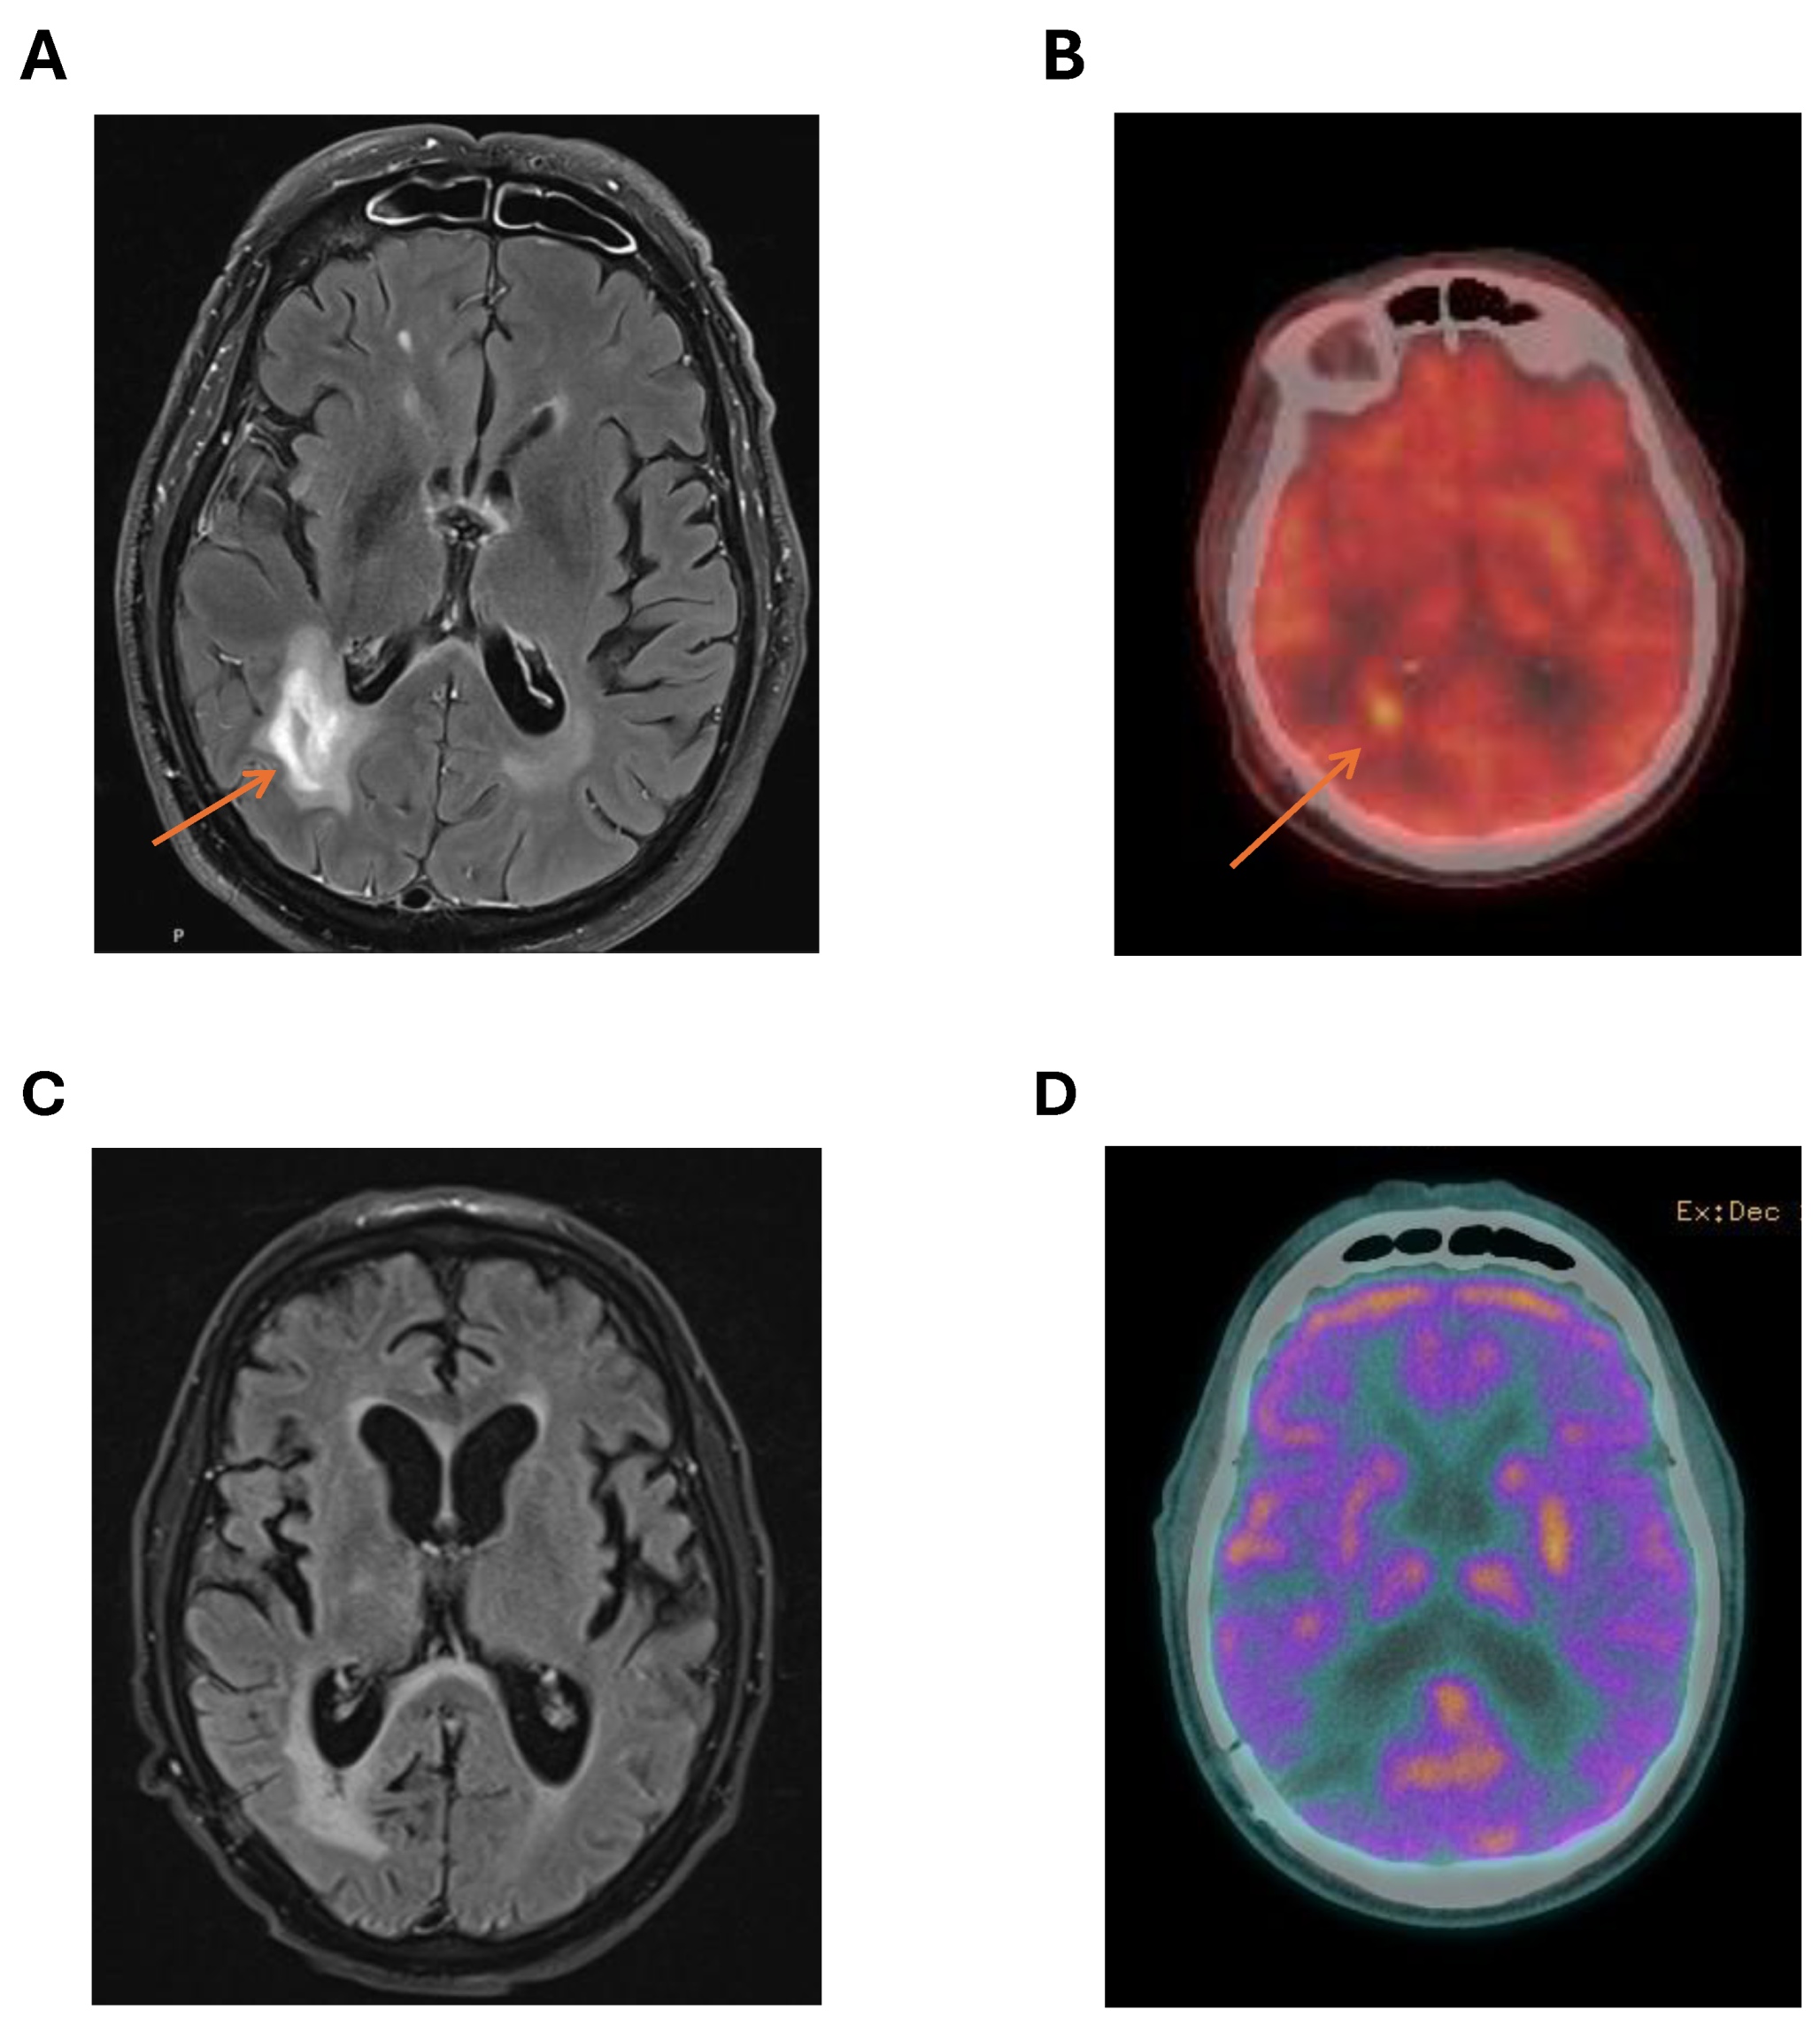

MRI brain provided better characterisation of the cerebral lesions with DWI and T2 flare enhancement of right parieto-occipital lesions (figure 1A). The most favoured diagnosis was cerebral lymphoma. A PET scan showed no FDG avid lesions outside the CNS with marked FDG avidity of the right parieto-occipital lesions (figure 1B). There was no ocular involvement with lymphoma. MRI spine was not performed. Testicular ultrasound showed no lesions suspicious for testicular lymphoma.

Following discussion at the institutional lymphoma multidisciplinary team meeting, treatment was commenced using the MATRix protocol (Methrotrexate, Ara-C, Thiotepa, Rituximab) with the plan to complete 4 cycles of induction therapy and then consolidate with carmustine and thiotepa conditioning therapy and autologous stem cell transplant (ASCT). MRI after 2 cycles showed significant reduction in the right parieto-occipital lesion. However, following cycle 3 of MATRix, the patient experienced significant therapy-limiting toxicities and complications including: severe renal impairment from methotrexate and delayed methotrexate clearance; moderate to severe lung-biopsy proven cryptogenic organising pneumonia (COP); pan-hypopituitarism; and COVID-19 infection. MRI (Figure 1C) and cerebral PET (Figure 1D) following cycle 3 showed further reduction in size of the right parieto-occipital lesion with reduced FDG avidity on PET (Deauville 3) suggestive of a complete metabolic response.

Figure 1. Characterisation of right parieto-temporal lesion at diagnosis with (A) MRI imaging showing T2 hyper-intense lesion; and (B) PET scan with markedly increased SUV in area of right parieto-temporal lesion compared to background FDG avidity. Imaging showing no residual enhancing lesion after 3 cycles of MATRix with (C) MRI and no T2 enhancement at site of original lesion and (D) cerebral PET with no FDG avid lesion in right parieto-occipital area. .